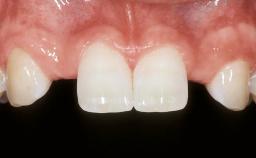

| Patient's Esthetic Expectations | Low | Medium | High |

| Lip Line | No exposure of papillae | Exposure of papillae | Full exposure of mucosa margin |

| Periodontal Phenotype | Low-scalloped, thick | Medium-scalloped, medium-thick | High-scalloped, thin |

| Shape of Tooth Crowns | Rectangular | Triangular | |